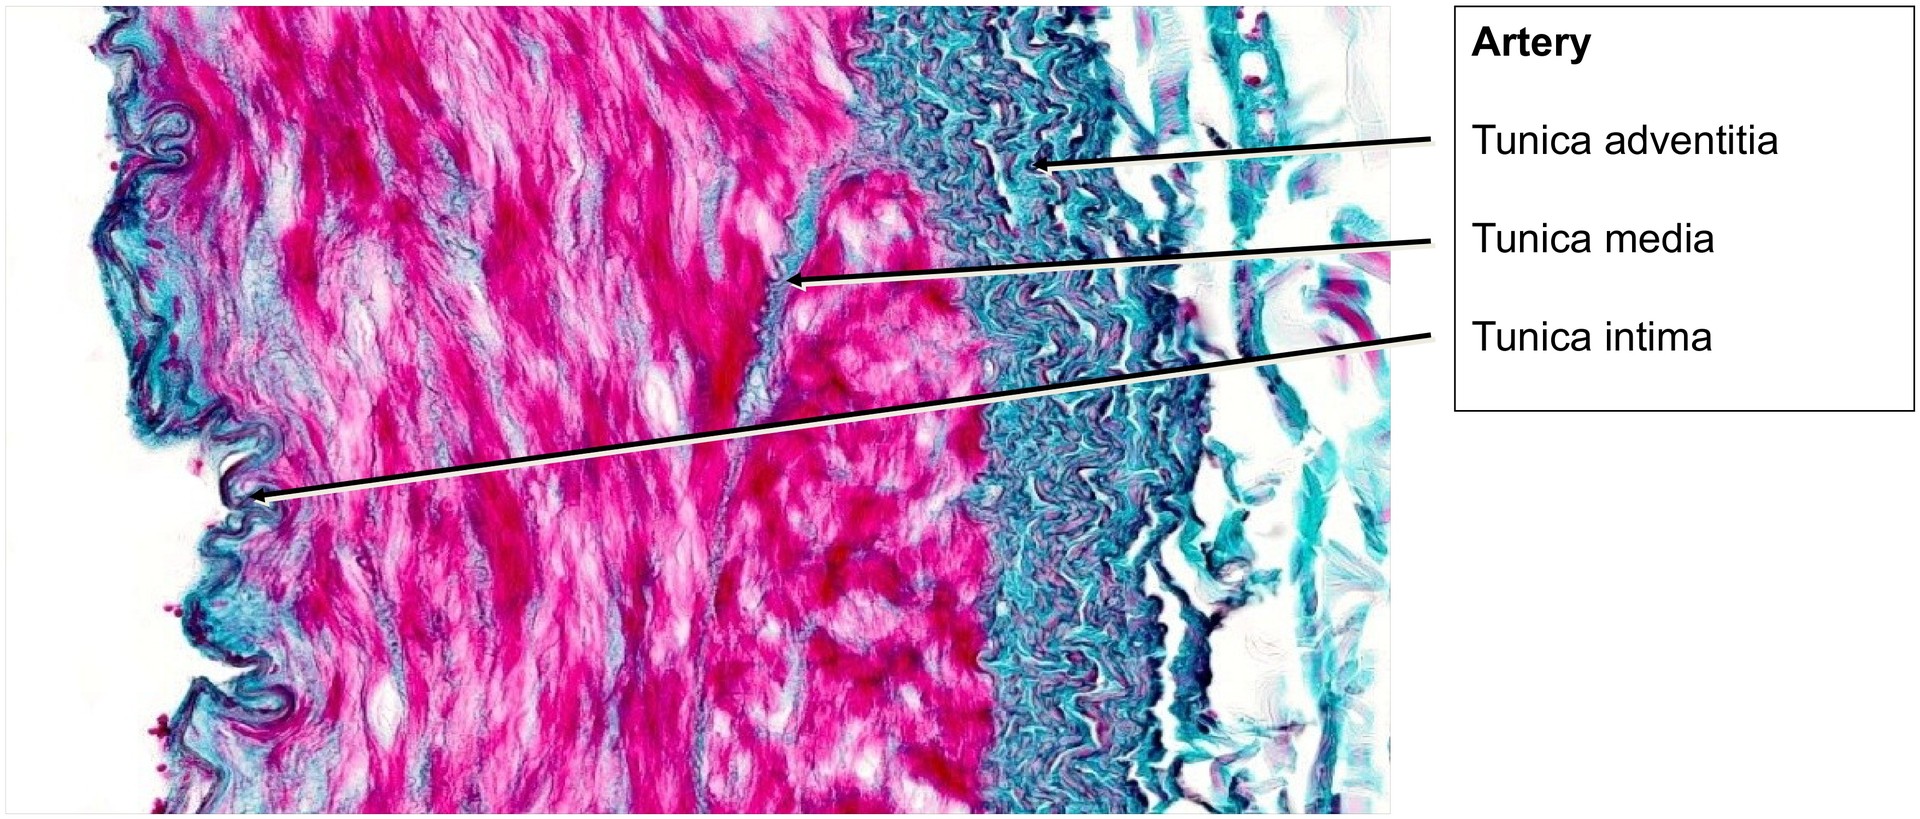

Artery:

- The endothelium lies directly on the internal elastic lamina; a subendothelial layer is only weakly developed (best seen at high magnification).

- The internal elastic lamina appears strongly convoluted due to contraction of the muscular tunica media during fixation.

- The media consists of smooth muscle cells interspersed with a few elastic fibres, markedly fewer than in the aorta.

- The adventitia is thinner and less distinct than that of the aorta, containing small connective tissue elements and vasa vasorum in some areas.